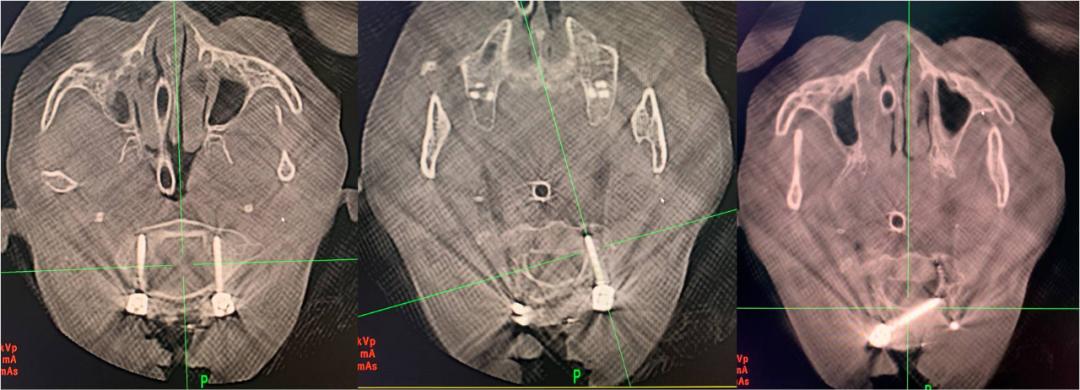

患者术前影像学检查结果

术中显露枕骨大孔周缘、寰椎后弓、枢椎棘突及椎板、寰枢椎侧块,枢椎棘突上放置示踪器,术中O-arm自动扫描获取寰、枢椎三维重建影像并传输至导航系统自动注册。

然后在导航图像引导下,在寰、枢椎选取最佳入点和角度植入椎弓根钉(枢椎右侧因椎弓根通道狭小、畸形而采用椎板钉固定)。

计算机导航引导下内固定植入术后O-arm扫描重建图像